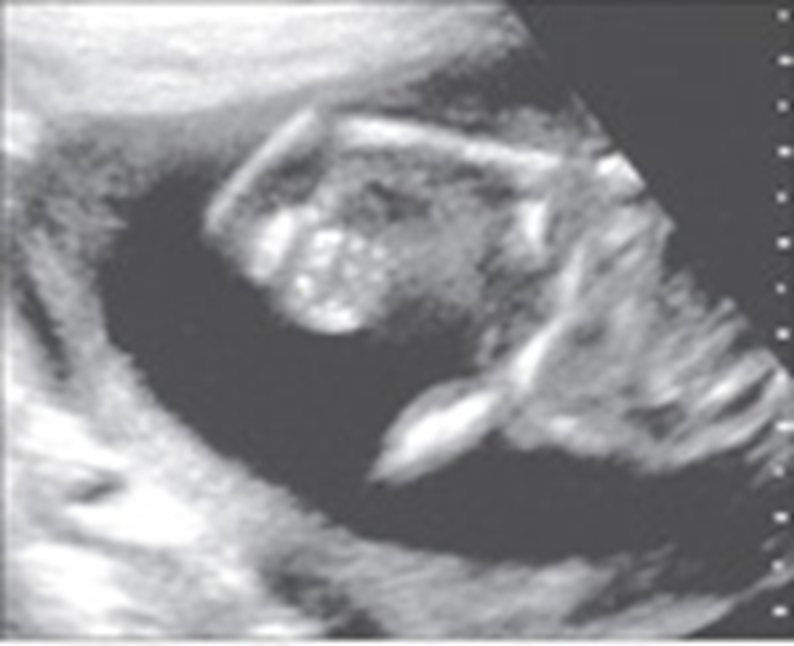

4 chamber view

Normal 4 chamber view

Identify structures of the heart